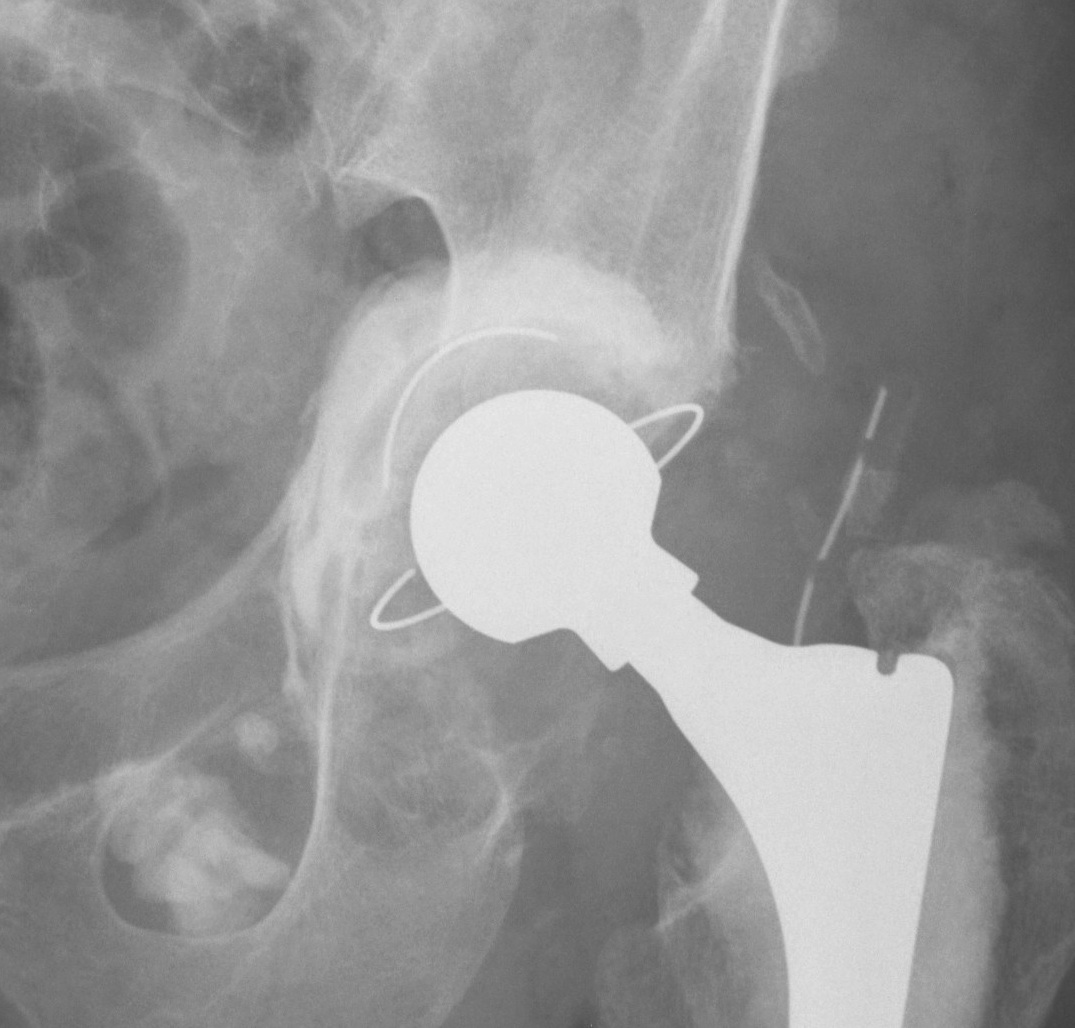

1. Uncemented Jumbo rim fit cup

Indications

- > 50% host bone available for ingrowth

- > 2/3 rim intact

Technique

- implant in usual position

- preferentially ream anteriorly

- preserve posterior column

- some uncovering superiorly allowed

- usually augment with screws

- +/- postoperatively NWB 6/52

Results

- 12-15 year survival between 81-96%